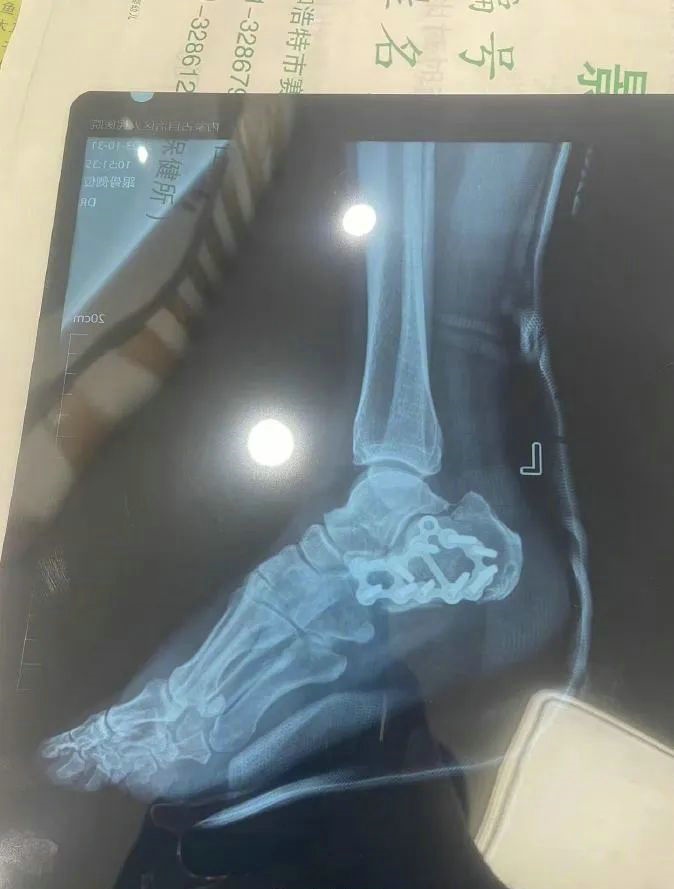

“那時(shí)候我剛工作了兩天,在第三天10月22日下午施工過程中從三層高的鐵架上摔了下來,導(dǎo)致30厘米左右的鋼筋刺穿我的右側(cè)臀部,左腳跟也粉碎性骨折,被送往內(nèi)蒙古自治區(qū)人民醫(yī)院救治,當(dāng)晚做了手術(shù)取出刺在右臀部的鋼筋,10月30日又進(jìn)行了左腳粉碎性骨折手術(shù)?!崩紫壬嬖V記者。